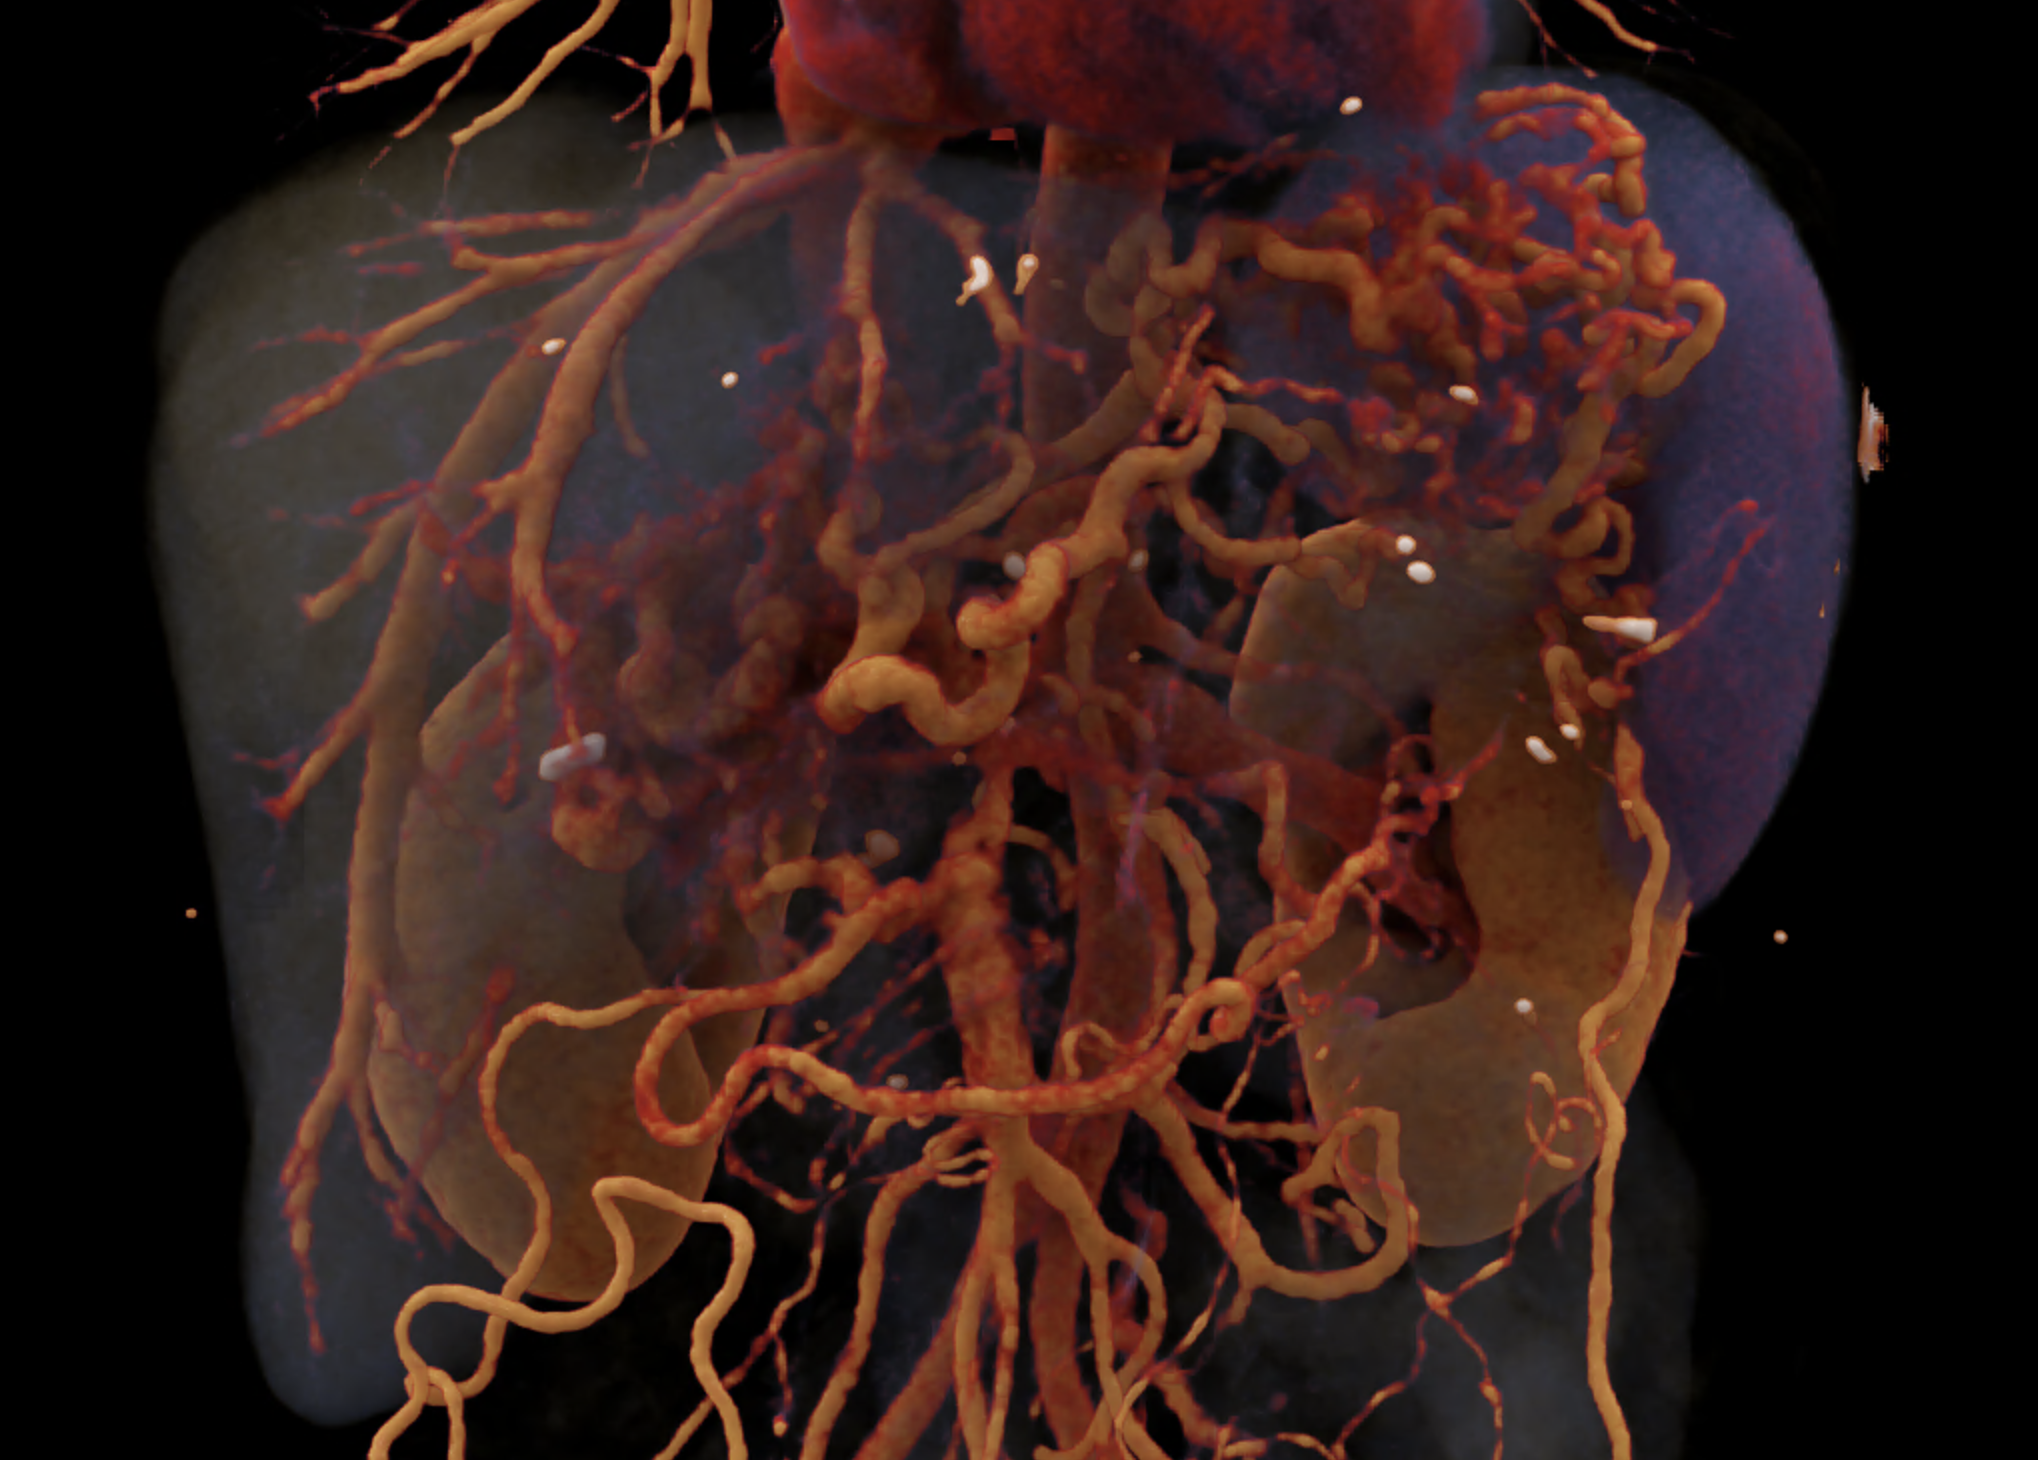

A patient with chronic pancreatitis and chronically occluded portal vein. The bile ducts have a significantly dilated wall, from the trunk, through the stump of the cystic duct, to the right and especially the left branch of the hepatic duct. At the same time, a large pseudocyst in the pancreas, dilatation of the pancreatic duct, and chromic occlusion of the superior mesenteric vein, splenic vein, and portal vein trunk are evident. Along with portal biliopathy, there is also arixy of the cardia and esophagus, as well as cavernous remodeling of the portal circulation itself.

volume rendered image after bone removal